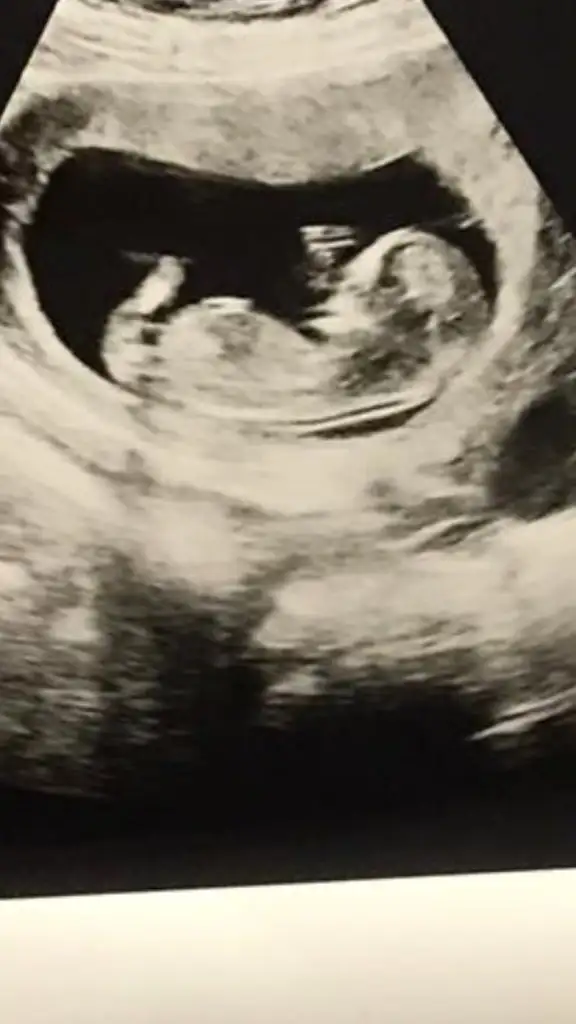

Eklentiler

• IMG_20210906_145002.webp

IMG_20210906_145002.webp

24 KB · Görüntüleme: 83

neyse bekleyelim bizde ozaman yapacak bisey yok benim ilk çocuğumda doktor.erkek demesine rağmen burda kiz demişlerdi 2015 te kızım var 😊 buda kardeşimin bakalım öğrenebilecek miyiz

Benimde kızımı bilmişti usg parlak olmasına ragmen. Şimdi yine kızım olmasını çokk isterim ama rabbimden hayırlısı tabi ki